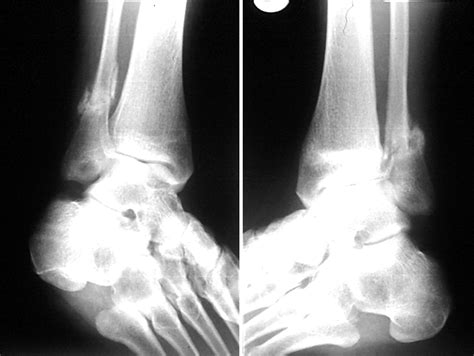

The fibula is the thin, long bone located on the lateral (outer) side of the lower leg. While it does not bear the majority of your body weight—the tibia carries most of it—the fibula serves as a crucial anchor point for various muscles that control ankle stability and foot movement. A Fibula Stress Fracture occurs when the bone is subjected to repeated force faster than it can remodel and repair itself. Over time, these tiny, microscopic cracks accumulate, leading to structural weakness.

• Point tenderness, where the pain is centralized in one specific spot along the fibula bone.

If you find that the pain persists for more than two weeks despite taking rest days, it is highly recommended to seek a professional medical evaluation, such as an X-ray or MRI, to confirm the diagnosis.